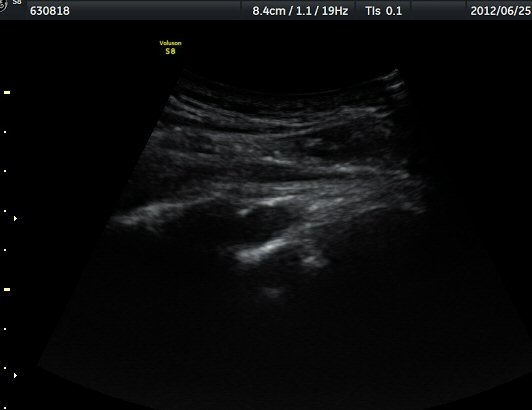

¿ª½Ã °ß°©°ñ °¡½Ãµ¹±â(spine) ¾Æ·¡¿¡¼­ Àú¿¡ÄÚ ³¶Á¾ÀÌ °üÂûµÈ´Ù(±×¸² 2). º¼·ÏŽÃËÀÚ·Î ¹Ù²Ù¾î °ü

ÂûÇÏ´Ï  °¡½Ãµ¹±â°üÀý¼ø°í¶û¿¡¼­ Àú¿¡ÄÚ ³¶Á¾ÀÌ ´õ¿í ¶Ñ·ÈÈ÷ °üÂûµÈ´Ù(±×¸² 3, 4).

ÁÖ»ç¹Ù´Ã ÈíÀÎ(µ¿¿µ»ó Âü°í) 4ÀÏ ÈÄ °üÂûÇÑ ¼Ò°ß¿¡¼­´Â ³¶Á¾ÀÇ Å©±â °¨¼Ò°¡ ¶Ñ·ÈÇÏÁö ¾Ê´Ù(±×¸² 5, 6).

ÈíÀÎ 14ÀÏ ÈÄ ÃÊÀ½ÆÄ°Ë»ç¿¡¼­ ¾à°£ÀÇ ³¶Á¾ Å©±â °¨¼Ò°¡ °üÂûµÈ´Ù(±×¸² 7, 8)